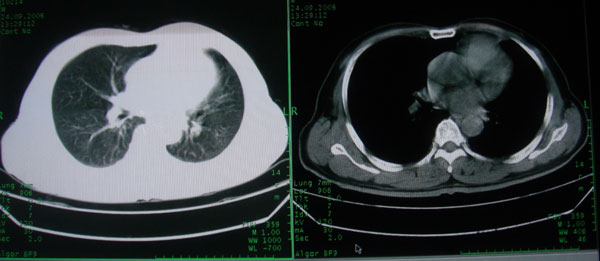

患者男性58岁因二周前起咳嗽,今天胸片示左上肺占位性病变行ct检查,无发热,无咯血痰.

左上肺感染性病变,结核伴空洞形成可能,左上肺膨胀不全

左肺上叶病灶,实变但见含气支气管、空洞但未见壁内结节及积液;

考虑:①感染性病变(包括特殊感染型肺tb)

②肿瘤性病变(考虑患者年龄比较大的关系/所以不排除)

初学者。。。左肺空洞性病变,并可见阻塞性肺不张改变,鉴于患者为老年男性,且临床症状仅有咳嗽,全身中毒症状不明显,所以我首先考虑为左肺癌性空洞并左侧肺门淋巴结转移伴左肺阻塞性肺不张。结核性空洞放于第二位考虑,可以进行相关实验室检查。希望能有病理结果,谢谢!!!!!

左肺上叶实变影,内见支气管充气征及空洞影,病人年龄较大,无发热及结核中毒症状,心影左移,未见纵隔淋巴结肿大;不知实验室检查结果如何?有否嗜酸细胞增多,有没有进行治疗?就目前资料首先考虑1.感染性病变,2.慢性嗜酸性肺炎?可结合实验室检查并短期治疗复查,肺癌不能排除。